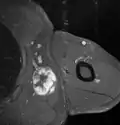

Medical ultrasonography and magnetic resonance imaging (MRI) of liposarcomas are helpful and often essential in determining their extent, surgical accessibility, and relationship to any observed organ dysfunctions. Since ultrasonography is usually unable to distinguish a liposarcoma from a benign lipoma, MRI is the initial imaging of choice to provide evidence relative to making this distinction.[67]

In myxoid liposarcoma, it shows low signal intensity mass with high signal intensity foci on T1-weighted MRI images. The mass shows high signal intensity on T2-weighted images. This is because it contains predominantly mucoid substance (accounts for low signal intensity on T1) and small amount of mature fat (accounts for high signal intensity on T1).[68] The mass is well-defined, lobulated, multiloculated, or oval in shape without any infiltration into surrounding structures.[68]